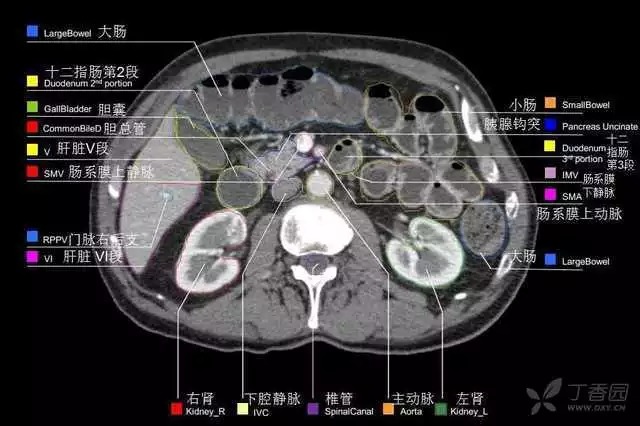

腹部肝脏高清CT断层的图谱

全腹部高清CT图谱,淋巴结彩色图谱,血管解剖图谱大汇总!

肝段,肝内管道的分布规律